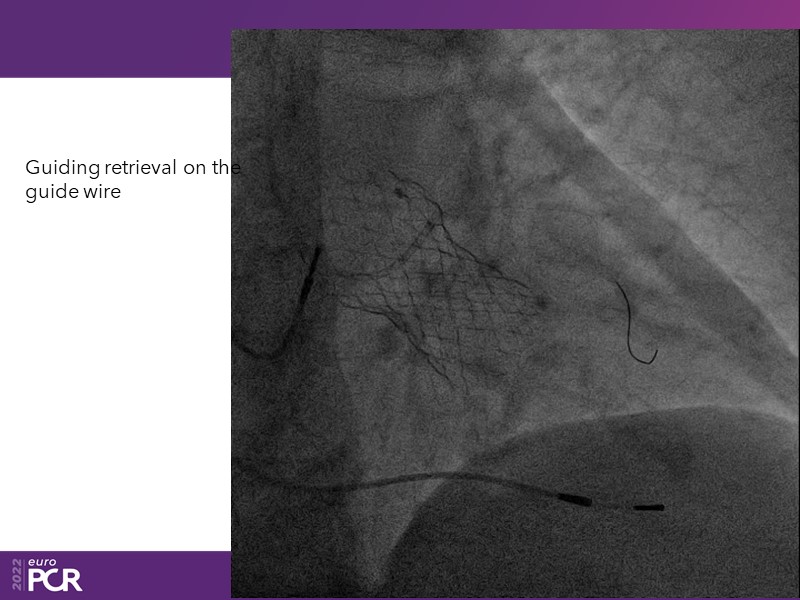

Consult this session to learn how to contribute to streamlined pre- and post-TAVI patient pathways, to discover updates on the optimised TAVI procedure and appreciate the variances in different valve designs and the long-term patient outcomes, as well as to discuss the right time of PCI in TAVI patients (steps on the procedure).